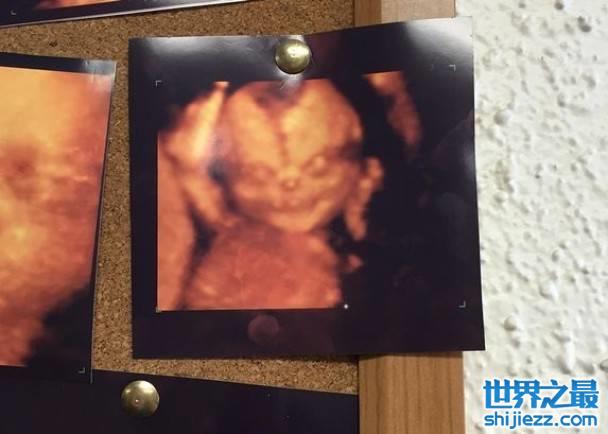

4D超声波照惊现恐怖胎儿照 英国夫妇吓出冷汗

社交网Reddit一名相信是准爸爸的用户,称日前与怀孕妻子到诊所,本希望为胎儿照4D超声波,但在诊所看到多张超声波照中,其中一张貌似恶魔般奇异的胎儿照,背部不禁冒出冷汗,两人随即打退堂鼓。他上载该照片后,网民迅即疯传,直言令人感不安。